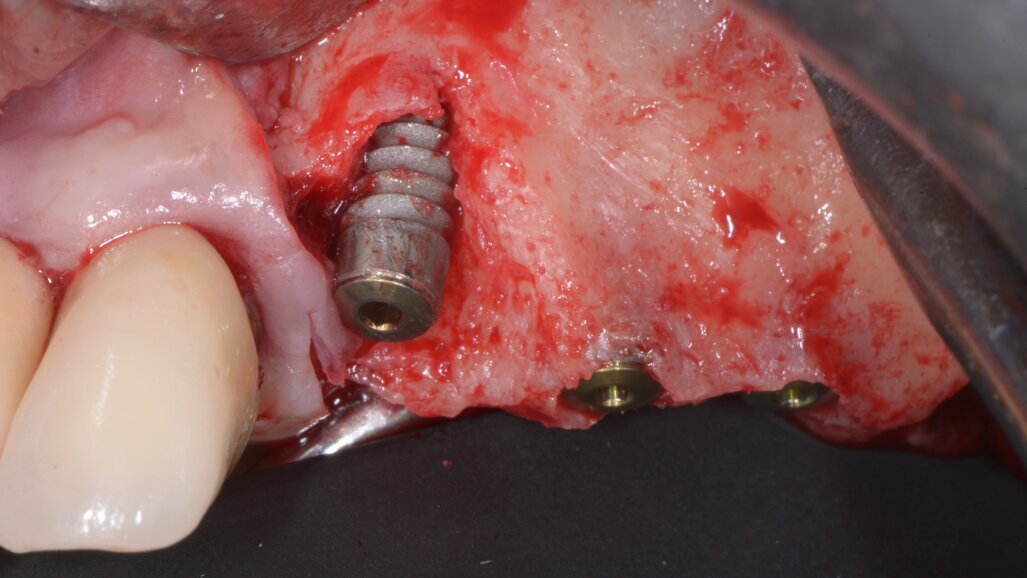

Quando le frese Densah successive avanzano nell’osteotomia, l’osso viene spinto (o densificato) verso l’estremità apicale e comincia a sollevare gradualmente la membrana di Scheneider con l’osso autologo compattato. Utilizzare sempre le frese con movimento di “pompaggio” e abbondante irrigazione, al fine di non surriscaldare l’osso. Per raggiungere una maggiore profondità verticale e il sollevamento graduale della membrana senza perforazioni si consigliano incrementi di 0,5 1,0 mm per fresa, fino ad ottenere la lunghezza e il diametro finale desiderato. Si ricorda che le frese in successione possono raggiungere un sollevamento della membrana di massimo 3 mm. Vista la scarsa qualità e quantità ossea residua del caso in questione, pur usando le frese Densah in modalità di osseodensificazione non si riesce a mantenere una integrità ossea della porzione apicale dei siti osteotomici (Fig. 5). Nei casi di incrementi superiori a 3 mm si può collocare all’interno dell’osteotomia del materiale da innesto, utilizzando l’ultima fresa con velocità di 150-200 giri/min senza irrigazione e in senso antiorario, per compattarlo all’interno dell’osteotomia. In questo caso si posizionano delle membrane di PRF all’interno dei siti osteotomici, così che la membrana di Schneider venga sollevata idrostaticamente con leggere pressioni del PRF (Fig. 6). Finita la fase di preparazione dei siti osteotomici si può procedere all’inserimento implantare a 20 giri/min e 50 Ncm di coppia (Fig. 7). Si esegue a questo punto un innesto di osso eterologo tipo “L-PRF-block”7 per incrementare il volume della zona vestibolare (Fig. 8). Sull’innesto vengono posizionate delle membrane di PRF assottigliate (Fig. 9) e una ulteriore membrana riassorbibile viene posizionata sopra il PRF per assicurare l’immobilità del tutto (Fig. 10). Si procede con l’esecuzione di scarichi di rilascio periostali, per avere un lembo privo di tensioni muscolari (Fig. 11). Infine, viene eseguita una sutura con filo 5 zeri riassorbibile monofilamento (Fig. 12). Nell’immediato post-operatorio viene eseguita alla paziente una CTCB di controllo. Come si può notare dalle sezioni della stessa, la membrana sinusale non risulta perforata, ed è sollevata sugli impianti (Figg 13, 14). Notare la neoformazione ossea apicale agli impianti a 5 mesi dall’intervento (Fig. 15).

Fig. 7 - Impianti posizionati in sede 23, 24, 25.